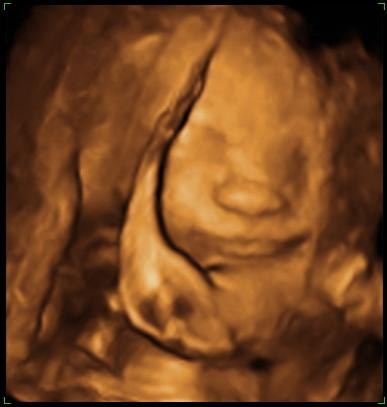

Så blev det endelig vores tur til scan igen, nøj det var jo bare vildt!!!

Orhh....hvor er mors lille <---- ( ? ) klump dejlig, nøjh nogen dejlig kinder.

Han blev målt til at jeg skulle være 1 uge længer fremme, men det kunne snyde op til 10% sagde hun.

Vægten sagde 1193.g